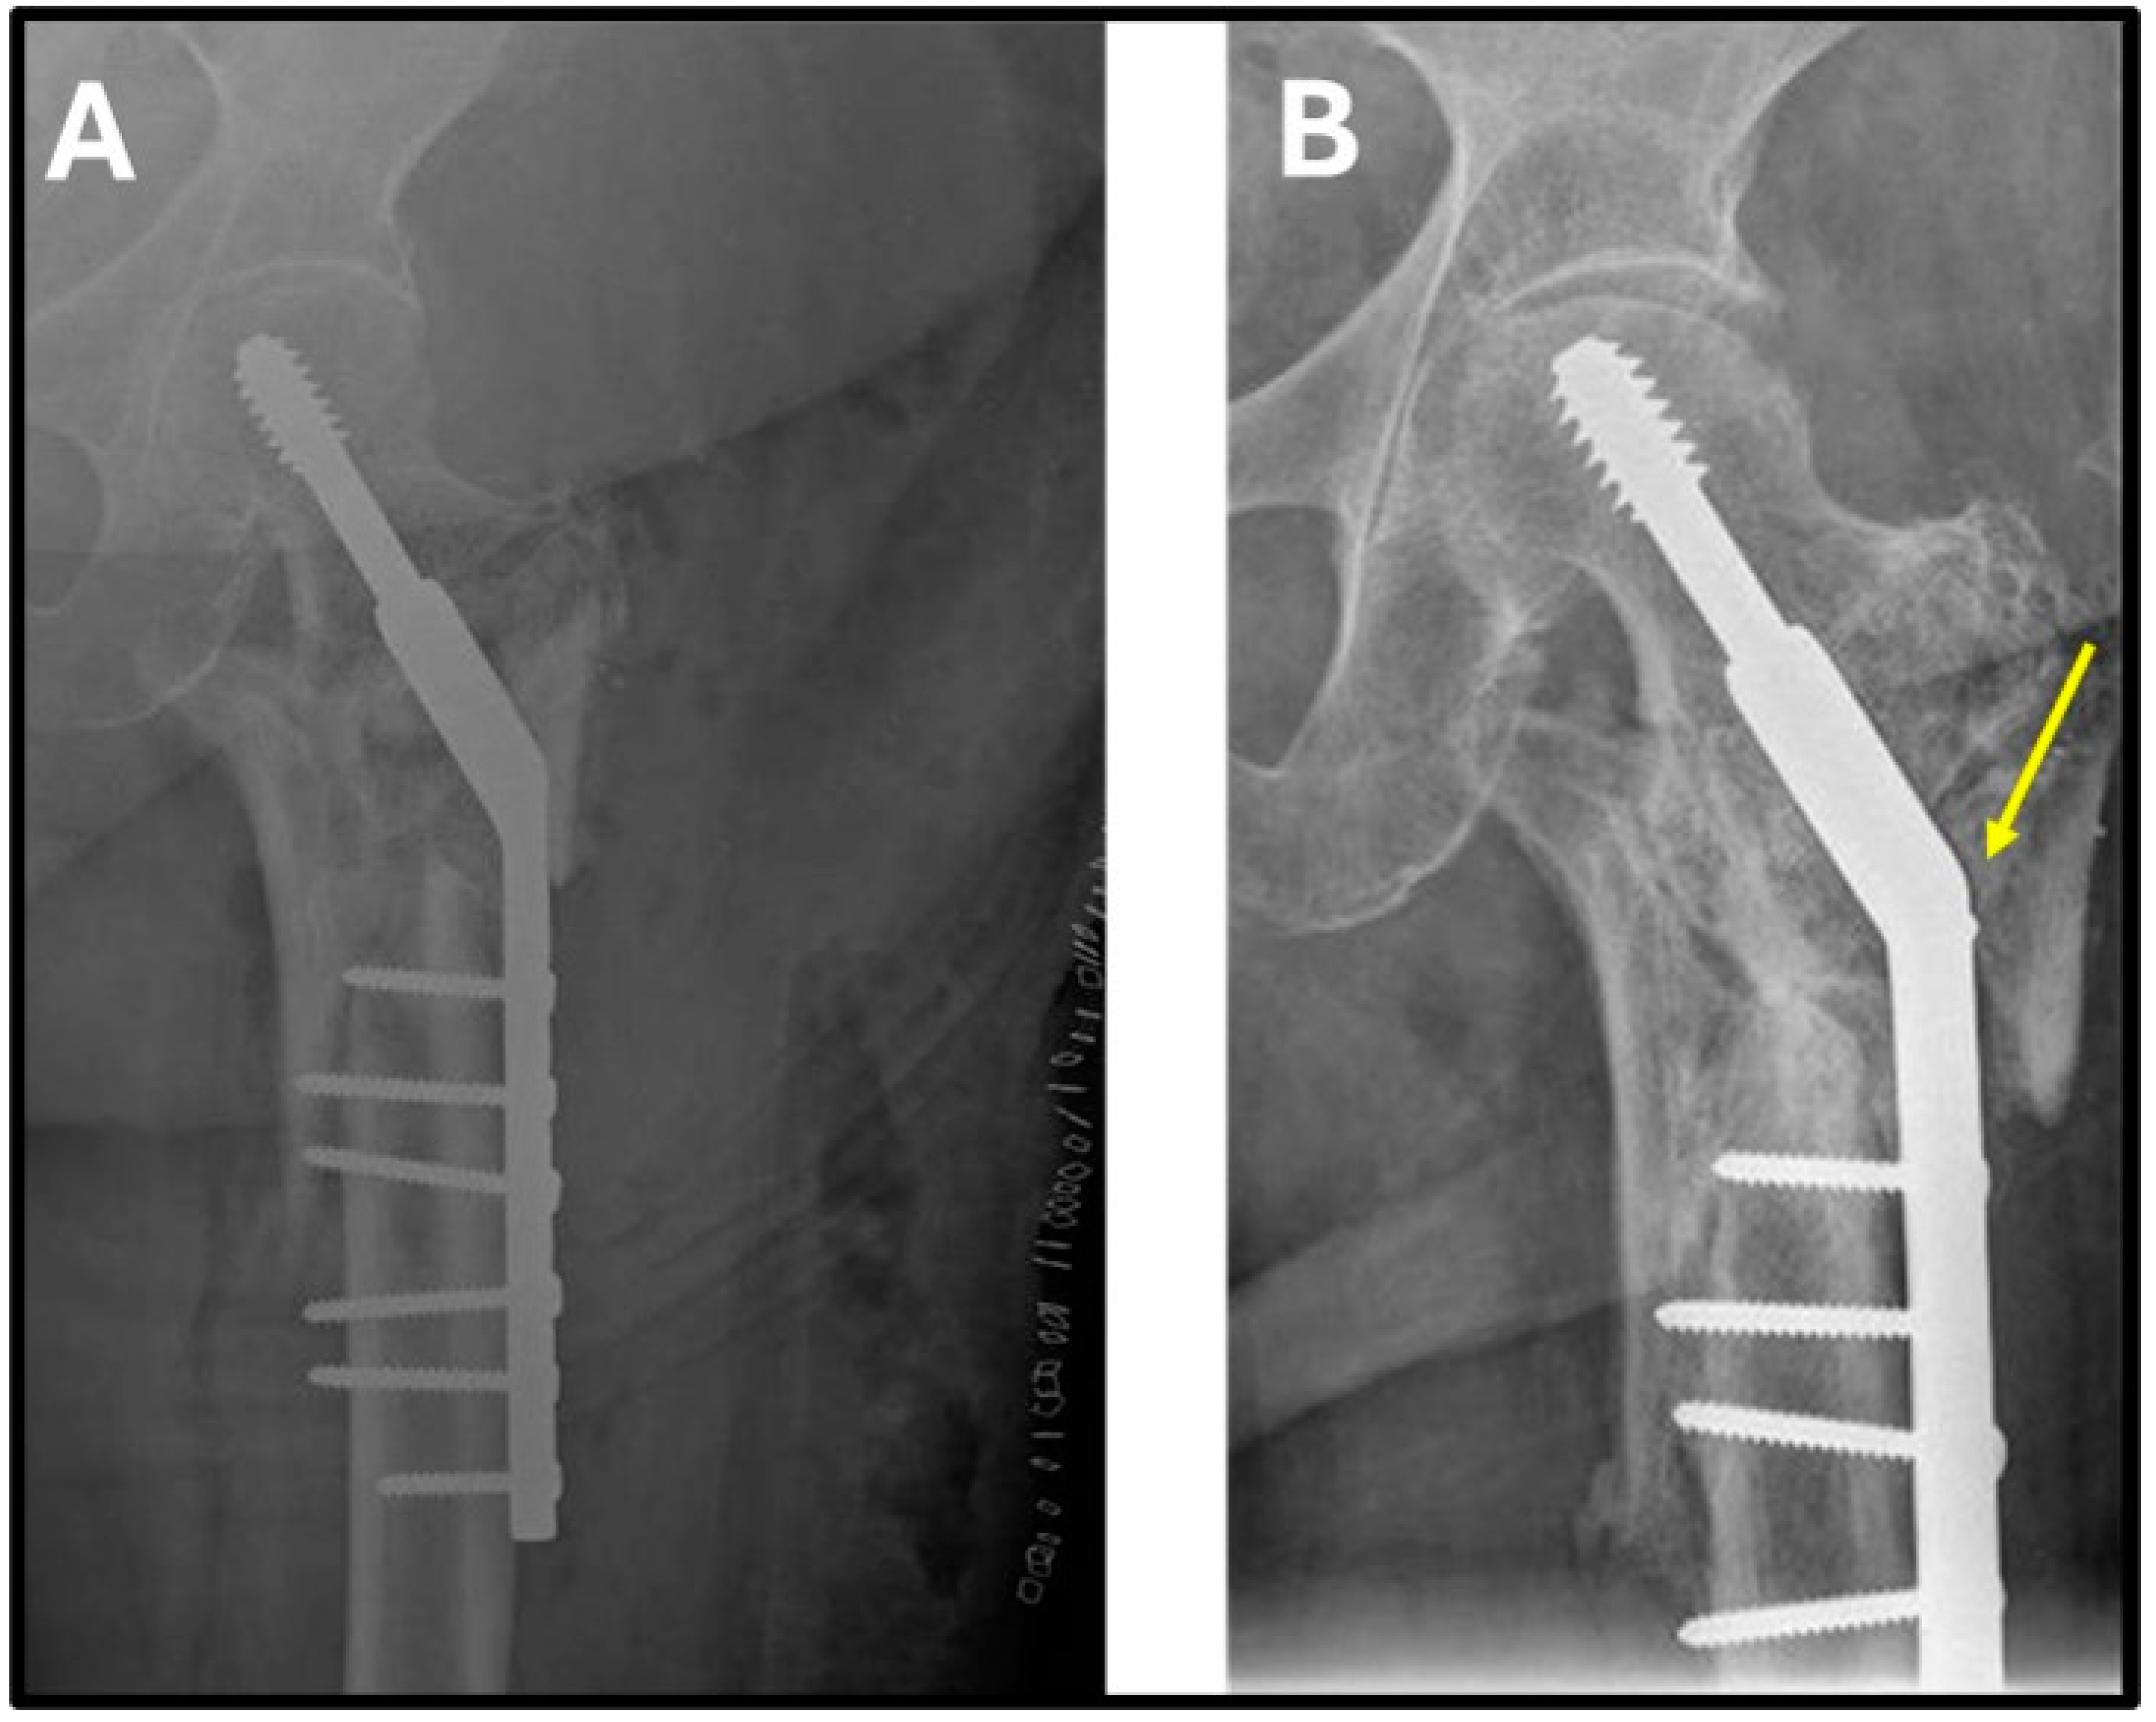

| Femoral neck angle pre-surgery * | 122° | 128° | 125° | 110° | 115° | 120° (110–122) |

| Pre-surgery offset (mm) * | 59 | 42 | 50 | 54 | 47 | 50.4 (42–59) |

| Vertical distance nonunion-head pre-surgery (mm) * | 57 | 43 | 32 | 46 | 40 | 43.6 (32–57) |

| Limb length discrepancy (mm) * | 12 | 8 | 9 | 4 | 7 | 8 (4–12) |

| Femoral neck angle post-surgery * | 142° | 150° | 150° | 147° | 145° | 146.8 (142–150) |

| Post-surgery offset (mm) * | 24 | 19 | 18 | 20 | 17 | 19.6 (17–24) |

| Vertical distance nonunion–head post-surgery (mm) * | 65 | 55 | 38 | 52 | 48 | 51.6 (38–65) |

| Postoperative leg lengthening (mm) * | 8 | 12 | 6 | 6 | 8 | 8 (6–12) |

| Time to union (months) | 4 | 6 | 6 | 5 | 4 | 5 (4–6) |

| Harris Hip Score post-surgery * | 96 | 96 | 88 | 90 | 88 | 90 (88–96) |